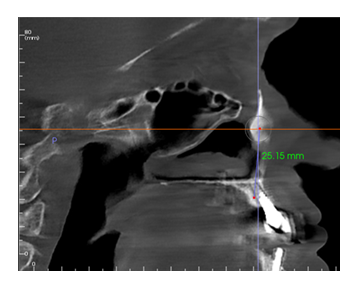

In this retrospective review, anonymized cone beam computer tomography (CBCT) scans from 300 sequential referrals were reviewed by the authors using PLACATE guidelines to determine transnasal dental implant feasibility. Inferior conchae were initially located in the coronal plane and imaging crosshairs were positioned just superior to this structure in the axial plane. To evaluate the ipsilateral and contralateral transnasal engagement points, imaging crosshairs were next positioned over each concha in the sagittal plane. This prelacrimal engagement point, sometimes referred to as the “Z-Point”, [4,5] was then evaluated according to PLACATE guidelines as follows: 1) Simmen classification [12] determined by measurement from the external aspect of the frontal maxilla to the most anterior aspect of the nasolacrimal canal (Figure 3); 2) Mediolateral measurement of prelacrimal bone width (Figure 4); 3) Vertical measurement of subnasal bone height (Figure 5); 4) Vertical measurement from subnasal bone to prelacrimal bone engagement point (Figure 6). To be considered an appropriate candidate for transnasal dental implants, the following parameters had to be met: 1) Simmen 2 or 3 classification; 2) Prelacrimal bone width ≥3mm; 3) Subnasal bone height ≥2mm; 4) Vertical measurement from residual subnasal bone, or anticipated anterior alveolar ridge reduction level, to prelacrimal bone engagement point that does not exceed 25mm. Failure to meet all four PLACATE criteria prevented a patient from being an appropriate transnasal implant.